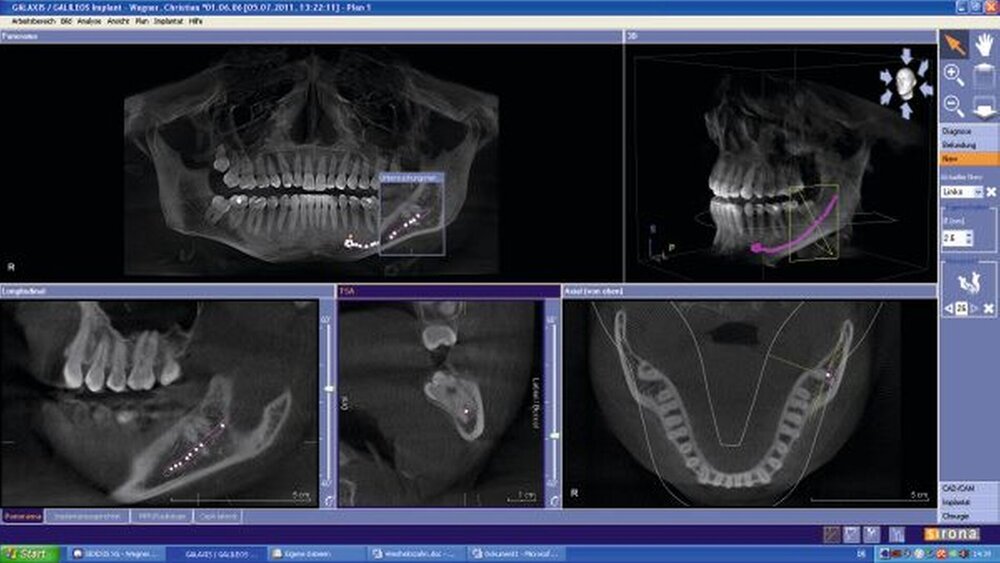

Im ersten Eingriff wird der perikoronale Knochen so weit abgetragen, um adäquaten Platz für einen ungehinderten spontanen Durchbruch des Zahnes zu schaffen. Zudem wird durch vorsichtige Subluxation die Beweglichkeit des Zahnes untersucht. Seine Entfernung erfolgt durchschnittlich sechs bis acht Wochen danach in einem zweiten Eingriff. Zuvor wird eine Panoramaschichtaufnahme zur Überprüfung der Zahnbewegung nach okklusal angefertigt.

Für die Studie wurden 17 Unterkieferweisheitszähne von 14 Patienten im Alter von 20 bis 47 Jahren durch einen Operateur behandelt. Alle Patienten waren zuvor radiologisch zwei- und dreidimensional untersucht worden. Bei Vorliegen gering mesioangulär und vertikal verlagerter dritter Molaren der Mandibula wurde die perikoronale Ostektomie durchgeführt. Nach dem ersten Eingriff zeigten alle 17 Weisheitszähne eine Wanderung von der unmittelbaren Nähe zum Canalis mandibulae in eine okklusale Ausrichtung, dabei betrug die durchschnittliche Wanderungsdistanz zwei Millimeter. Die Zähne wurden anschließend extrahiert.